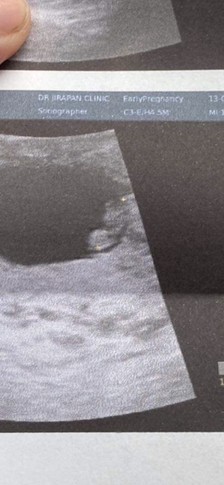

ตัวจิ๋ว9wแล้วว🎉

มีแม่ๆบ้านไหนซาวด์ตอน9วีคแล้วเห็นตัวเท่านี้บ้างไหมคะ หรือ มีแขนขา ครบกว่านี้ แต่บ้านนี้เพิ่งมีแขนจิ๋วๆออกมา ตื่นเต้นมากตอนเห็นหัวใจน้อง มันดีใจไปหมดเลย🥹👶🏻🤍

ตอนเรา 9วีค เห็นแบบนี้เหมือนกันค่ะแม่ เป็นก้อนๆมีแขนขาเล็กๆแง่งๆออกมาแล้ว เพราะยังจิ๋วมาก 🥰🥰🥰🥰

ของเราตอน9วีคค่ะแม่ ตัวจี๊ดนึง😂